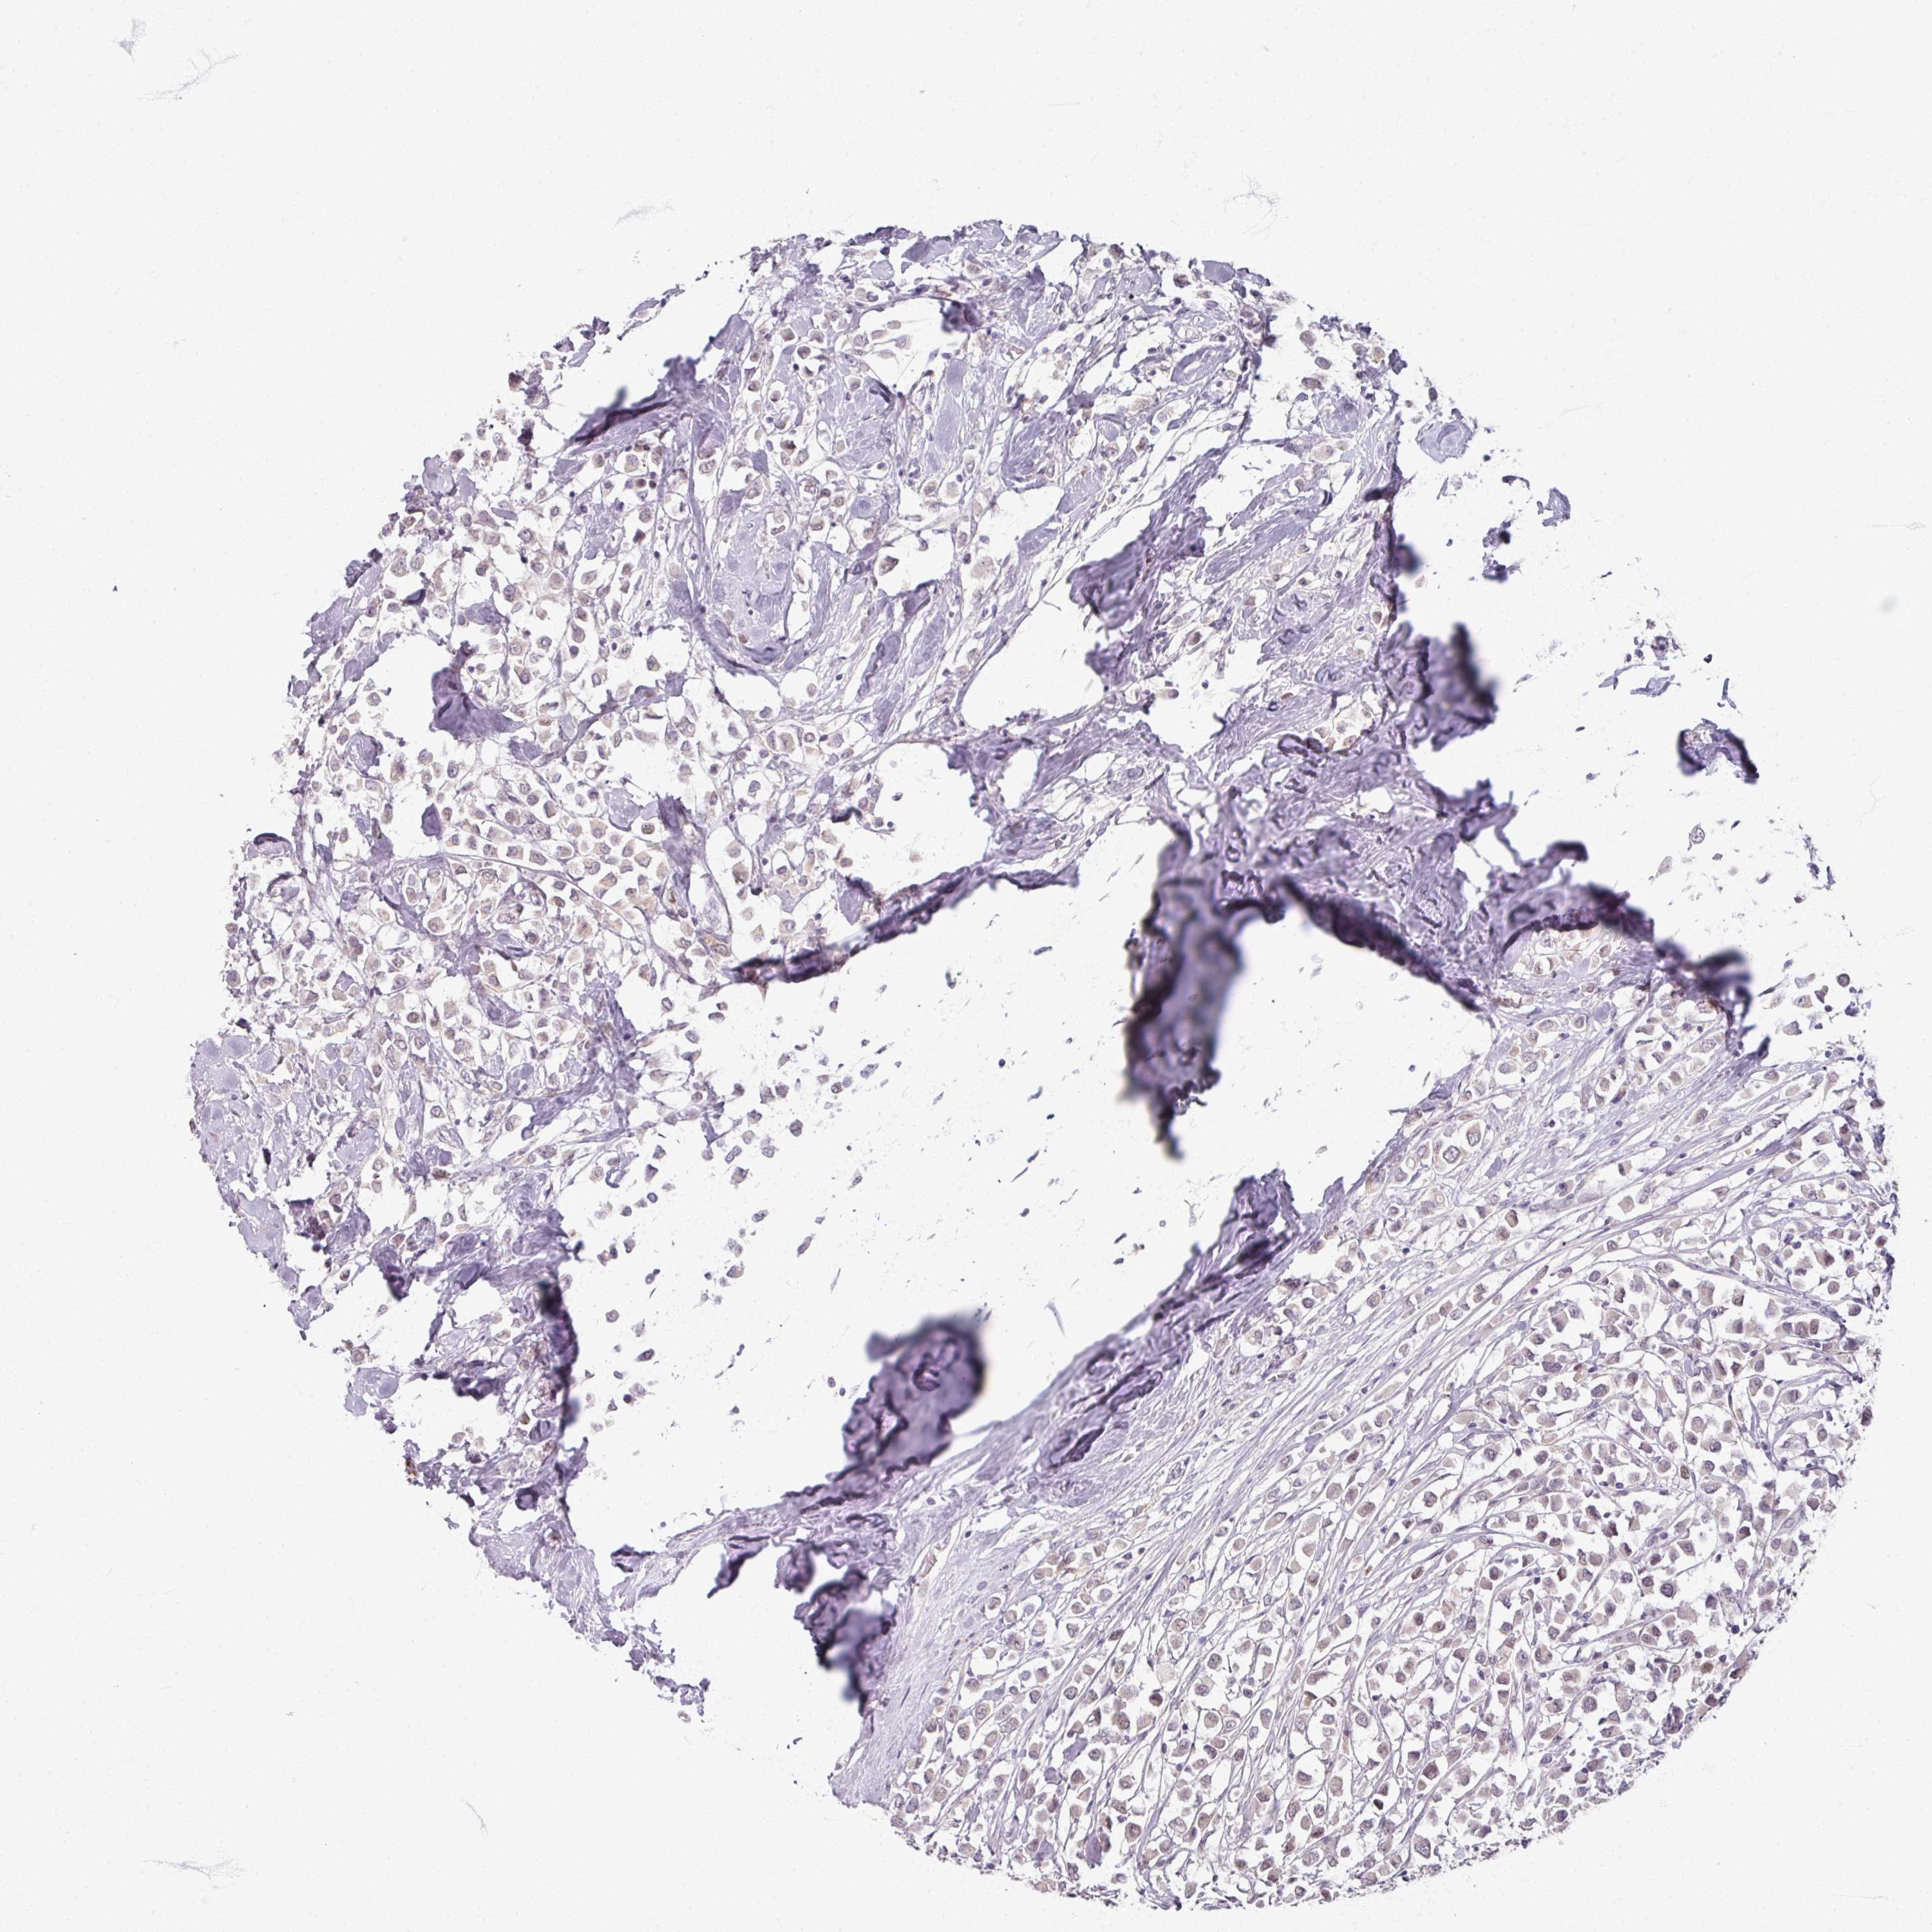

CANCER BREAST CANCER Show tissue menu

BRCA TCGA BRCA VALIDATION PROTEIN EXPRESSION

ANTIBODIES

AND

VALIDATION